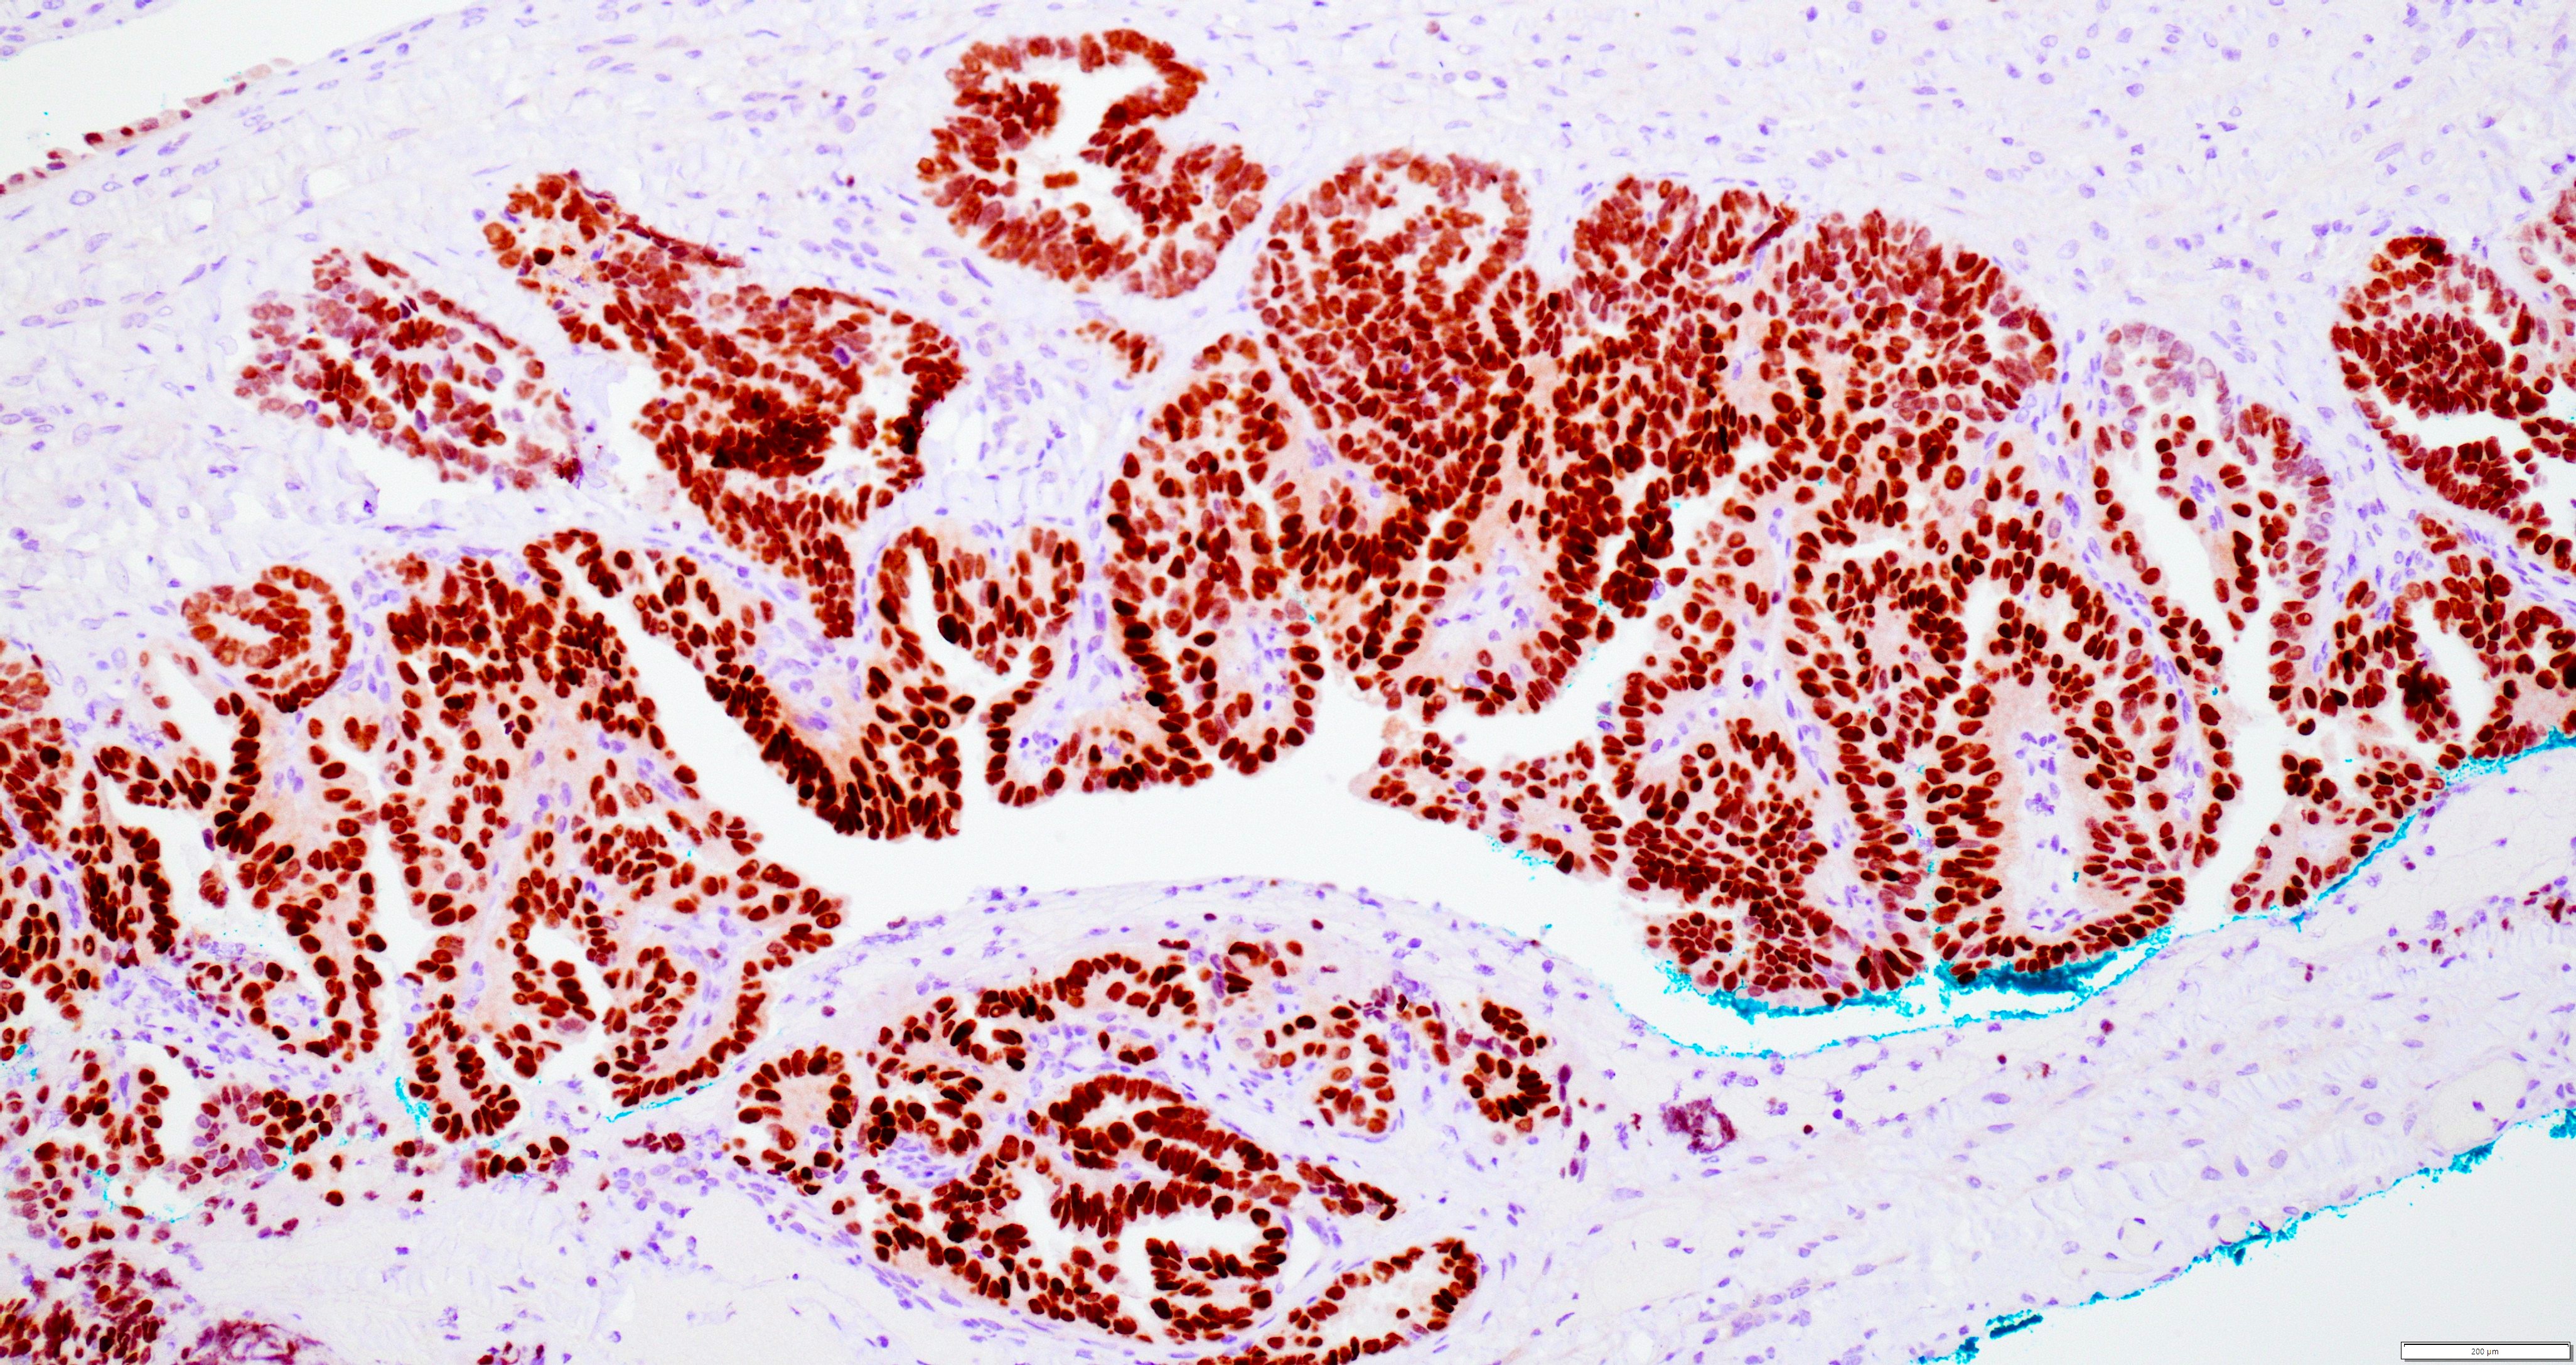

Microscopic (histologic) images

Contributed by Daniel Graham, M.D., Adele Wong, M.B., B.Ch., B.A.O. and Lucy Ma, M.D.

Positive stains

- PAX8: usually diffusely positive

- GATA3 and TTF1: focal or diffuse with inverse staining pattern described in several studies in the most recent WHO classification; cells positive for GATA3 are negative for TTF1 and vice versa (Am J Surg Pathol 2018;42:1596)

- CD10: focal and apical / luminal

- p53 wild type

- MMR proficient